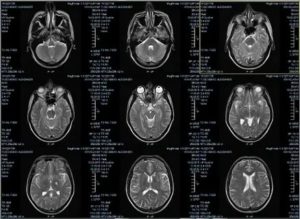

Результаты МРТ исследования врач-диагност получает в трехмерных срезных снимках мозга, а пациент получает изображение на носителе или на почту.

МРТ головного мозга здорового человека показывает целостный орган, без патологических очагов и смещений структур.

Описание заболеваний на сканировании:

МРТ при опухоли.

На снимке новообразование имеет вид несимметричного белого большого пятна, которое имеет рваные края. Это пятно может смещать соседние структуры головного мозга, из-за чего на снимке желудочки и пространства уменьшаются в размере. Когда растет опухоль, появляются новые сосуды. Это видно на ангиографической магнитной ангиографии.

Инсульты.

Ишемический инсульт – это область мозга, где недостает крови. Так, на снимке эта зона выделяется более светлым участком, в отличие от соседних зон. Однако в отличие от новообразования, это светлое пятно будет располагаться в области магистрального сосуда. Если применить ангиографию, то в области ишемии контрастирование снижается.

Геморрагический инсульт – это кровоизлияние в мозговое вещество. На снимке это выглядит как затемнение на МРТ в области магистральной артерии, окруженный темной полосой.